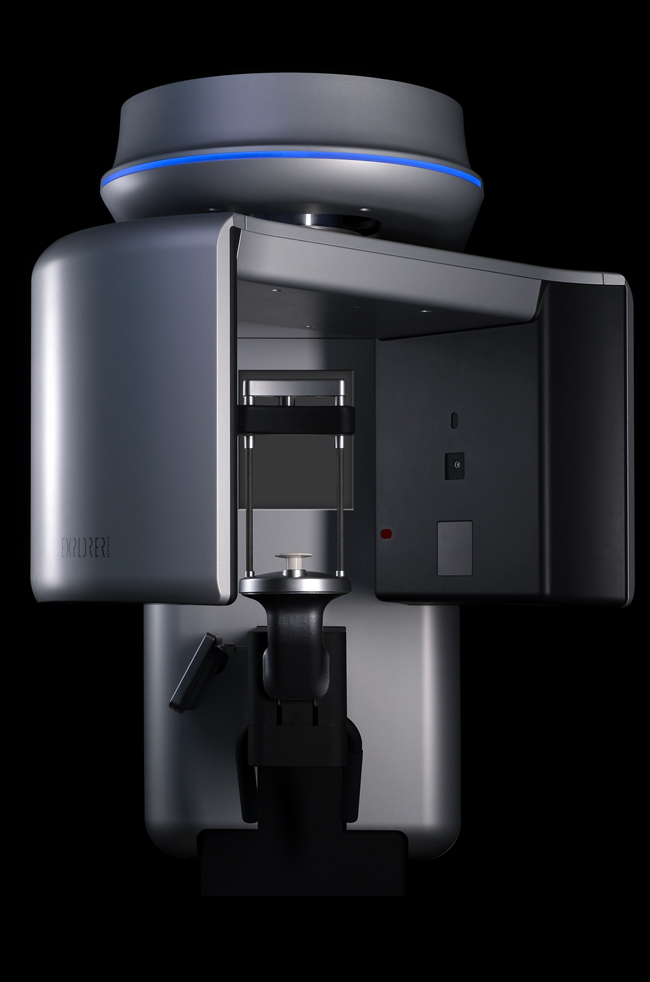

Com um dos maiores FOV do mercado, 150 mm x 160 mm, o PreXion3D EXPLORER pode exibir todas as estruturas anatômicas importantes do crânio em detalhes. O poderoso software de imagem ajuda a destacar e medir as áreas de interesse. Especialmente para cirurgia oral e maxilofacial, bem como na medicina do ouvido, nariz e garganta. A análise de imagens espaciais em grandes áreas ajuda a desenvolver as melhores opções de terapia.

que PreXion3D EXPLORER?

Os poderosos componentes do sistema do PreXion3D EXPLORER e a combinação extraordinária das mais precisas imagens 3D, com grandes detalhes e menor exposição à radiação, permitem diagnósticos confiáveis e planejamento digital para todas as indicações da odontologia moderna, como periodontologia, endodontia, implantodontia e cirurgia maxilofacial . O sistema de gerenciamento de pacientes foi projetado para comunicação segura dos dados do paciente em toda a rede do cliente podendo ser integrado à infraestrutura existente. Com a precisão e competência profissional da PreXion, os clientes têm o parceiro certo ao seu lado.